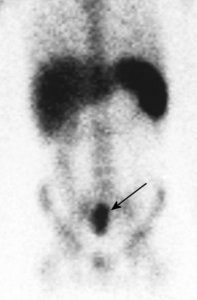

Metastatic prostate cancer on In-111 WBC imaging: The patient below was being evaluated for a fever of unknown origin. The WBC study revealed photopenic lesions involving the spine due to prostate metastases. |

|